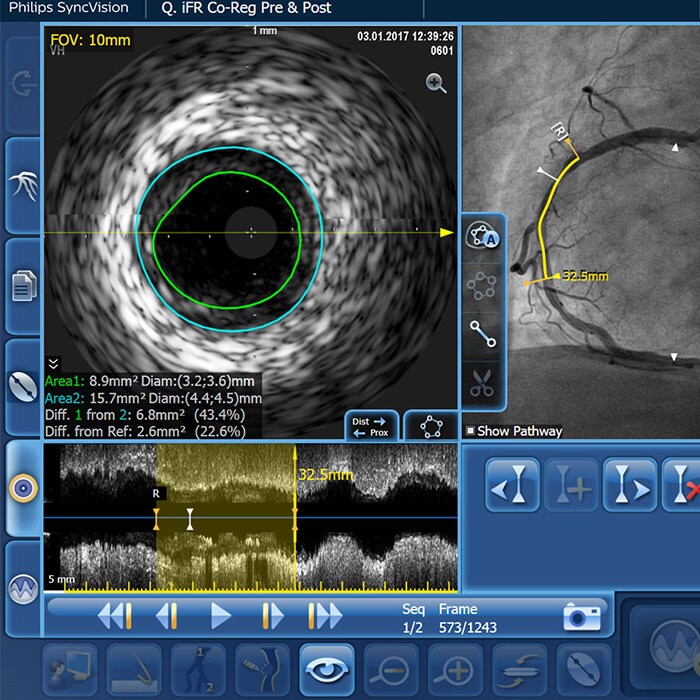

– Diffuse CAD may be underestimated by evaluation with coronary angiography.

– Determining reference vessel sizing can be challenging when the vessel is diffusely diseased.